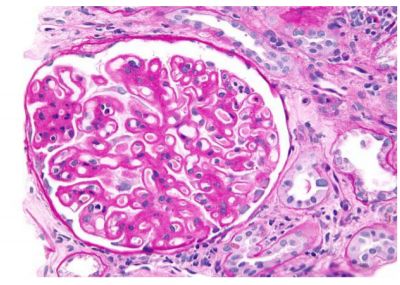

14. 某66歲病人因尿蛋白3+,血清白蛋白2.9 gm/dL,BUN 27 mg/dL, Cre 1.5 mg/dL, 經腎臟穿刺檢查為膜性腎病變,其病理如附圖(A、B、C、D), 請問其腎臟病與下列何者沒有關聯? (A) 梅毒 (B) B型或C型肝炎 (C) 抗Phospholipase A2 receptor抗體 (D) 抗Soluble urokinase plasminogen activator receptor抗體 (E) 惡性腫瘤